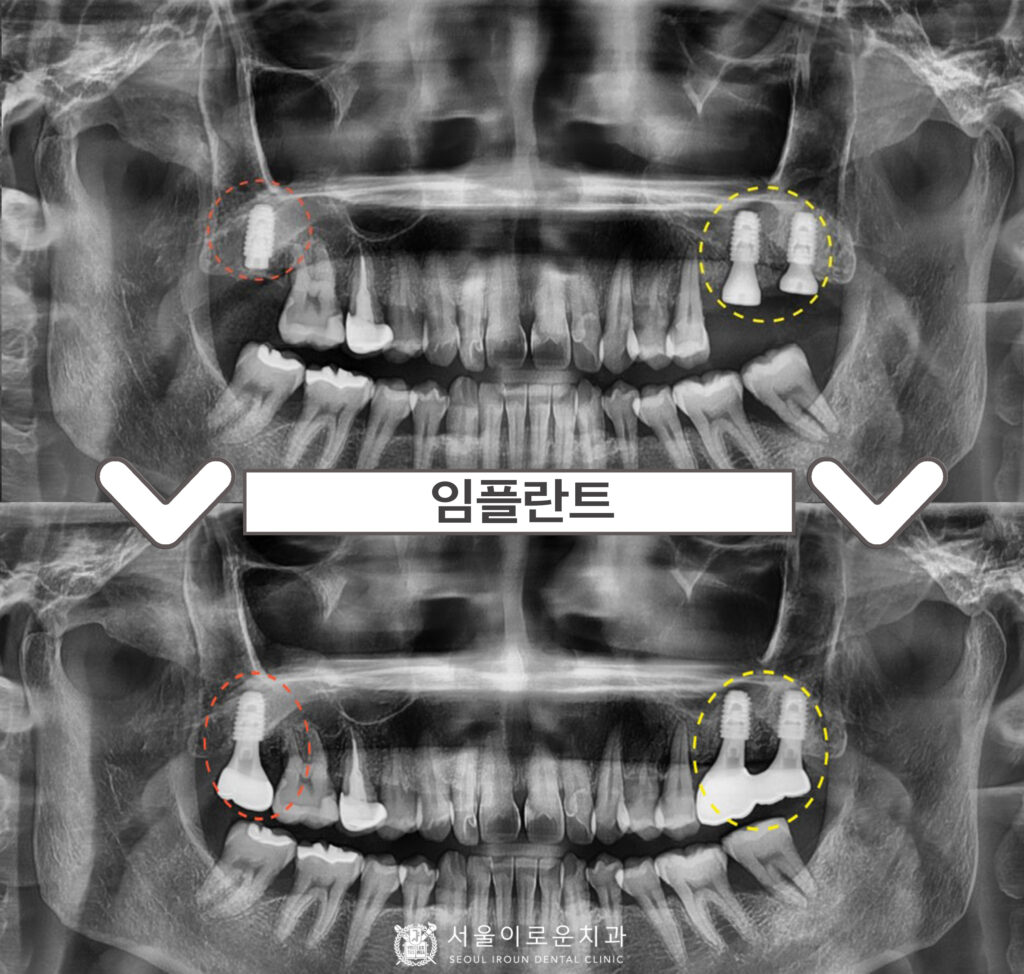

정밀한 검사를 위해

파노라마 사진을 촬영해 보았더니,

✅ 노란색 동그라미 표시의

위턱 왼쪽 큰 어금니 두 개(#26,27)는

심한 치주염으로 인해

2도 동요도를 보이고 있었는데요.

치아 뿌리를 잡고 있는 잇몸뼈가

염증으로 인해 흡수가 많이 되어 있어

살려 쓰기 힘들 것이라 판단되어

안타깝게도 발치 후

임플란트를 계획했습니다.

✅ 빨간색 동그라미 표시의

위턱 오른쪽 두 번째 큰 어금니(#17)는

발치하신지 상당 기간 지났으며,

잇몸뼈에서 상악동까지의

수직적 거리가 충분하여

별도의 뼈이식 없이

임플란트 식립을 계획하였습니다.

양측 임플란트 식립 후 3~4개월 뒤

osstell beacon이라는

골 유착을 확인할 수 있는

장비를 이용하여

isq 측정하여 뼈와 임플란트가

잘 결합한 것을 확인한 뒤

보철 과정을 진행하였는데요.

임플란트 / 신경치료 + 크라운수복

치료를 모두 마무리 한 모습입니다.

✅ 전 > 후 ✅

(2024.03.02ㅡ>2024.08.15)